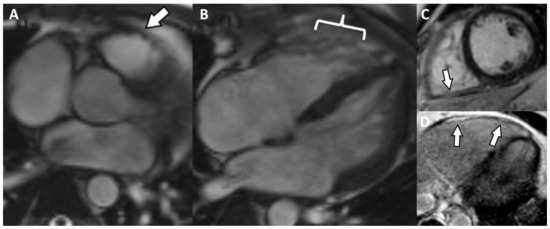

5. Cases Presentation